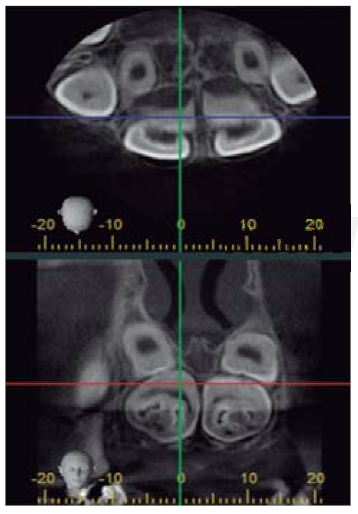

In order to assess the patient, panoramic X-rays were taken as well as an imaging study by means of computerized axial tomography. Intraoral examination revealed healthy mucosae and expansion of the cortical bone in the anterior section of the upper jaw, ankylosis, presence of palatal tori and mandibular bilateral tori (Figure 1). General physical examination revealed bilateral bone excrescences in the upper section of the shoulder blades. At a later date a colonoscopy was conducted in order to assess presence of intestinal polyps as well as association to Gardner's syndrome (which proved to be negative).

From the radiographic perspective, two radio-opaque areas surrounding the crowns were observed at teeth 12, 21, 22. At both lower premolar areas, a radio-lucid halo was observed (Figure 2). Presumptive diagnosis was proposed to which effect the following was effected: local anesthesia with 2% lidocaine carpulae (1:80,000) as well as surgical approach with number 3 Bard-Parker scalpel, total enucleation of tumor lesions with gubia type pliers, straight apical elevators, extraction of supernumerary teeth with angulated elevators, synthesis with non-resorbable suture and needle. Anti-inflammatory medication was prescribed for the postoperative period and the patient was remitted to the Orthodontics and Maxillary Orthopedics section. The patient's mother received recommendations. After the procedure, previous diagnosis was replaced for one of complex odontoma due to confirmation provided by morphological characteristics and later histological examination, in addition to supernumerary teeth confirmation (Figures 3 and 4). Microscopically, the lesion was composed of a disorganized mixture of dental tissues, among which dentin, enamel, pulp tissue and cement could be found, as well as some foci of odontoblastic cells. No malignancy characteristics were found in analyzed samples (odontomas).